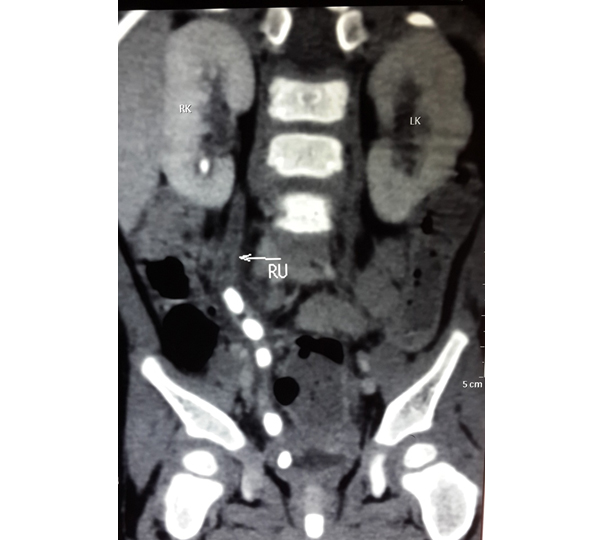

Vesico-ureteric reflux (VUR) occurs when the valve between the ureters (the tubes that carry urine away from the kidneys) and